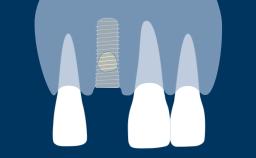

Os pacientes desejam dentes com boa saúde, função, estética e fonética. Quando indicado para dentes ausentes, os implantes dentários são um meio para atender a esses requisitos. Este Módulo de Aprendizagem delineará as geometrias dos implantes e suas características que visam facilitar a integração com os tecidos duros e moles, permitindo que eles sirvam como elementos de ancoragem para reconstruções protéticas enquanto também resistem às forças de carga oclusal.

A geometria do corpo dos implantes geralmente pode ser dividida em três partes: a parte endóssea, que se encontra dentro do osso, a seção transmucosa, que fica nos tecidos moles entre o osso e a cavidade oral, e a interface com os componentes protéticos. Em cada uma dessas três partes, existem outras características da geometria e variações na sua forma, atributos e dimensões. Existem também variações no material do corpo do implante e no tratamento de superfície. Essas variações serão descritas e discutidas nos seguintes Objetivos de Aprendizagem.

- descrever as variações da seção transmucosa do implante